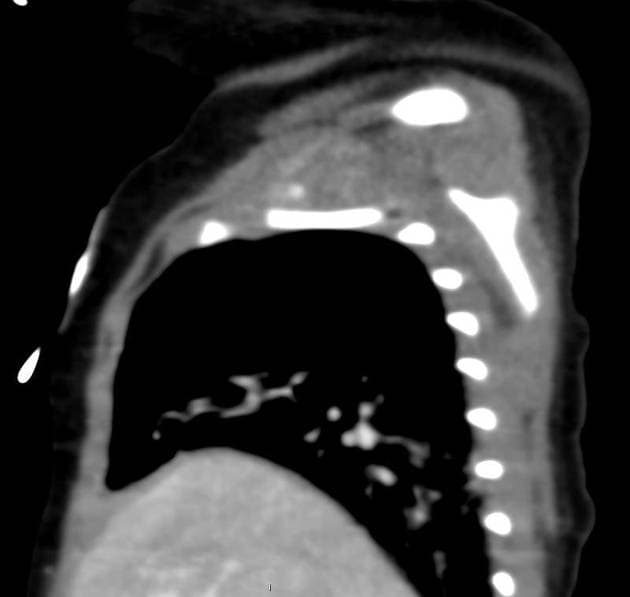

Series (5)

Axial C+ portal venous phase

Tái lập tĩnh mạch chủ trên (superior vena cava - SVC) với tĩnh mạch chủ trên phải (right SVC) có vị trí bình thường nhưng đường kính nhỏ hơn bình thường.

Tĩnh mạch chủ trên trái (left SVC) đổ vào tâm nhĩ phải thông qua xoang vành (coronary sinus).

Có sự thông nối giữa tĩnh mạch chủ trên trái và phải qua một tĩnh mạch nhỏ nằm ở phía trước, tương ứng với tĩnh mạch cánh tay đầu trái (left brachiocephalic vein), nằm trước động mạch chủ (aorta).

Tĩnh mạch phổi trên trái và tĩnh mạch phổi dưới trái đổ vào tĩnh mạch chủ trên trái (left SVC) thay vì đổ vào tâm nhĩ trái, phù hợp với tình trạng hồi lưu bất thường một phần của tĩnh mạch phổi (partial anomalous pulmonary venous return - PAPVR).

Động mạch dưới đòn phải bất thường (aberrant right subclavian artery) xuất phát từ cung động mạch chủ trái đoạn xa và đi sang bên phải, đi qua phía sau thực quản (esophagus).

Ngay phía dưới vị trí này là hẹp eo động mạch chủ (coarctation of the aorta).

Có ống động mạch (ductus arteriosus) hoặc PDA nhỏ tại vị trí dây chằng động mạch (ligamentum arteriosum).